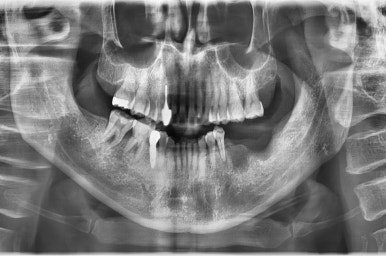

앞니 임플란트 진행중간 사진

어금니 임플란트와 앞니 임플란트를 하여

환자분이 편안한 식사생활과 사회활동을 할 수 있게 하였습니다.